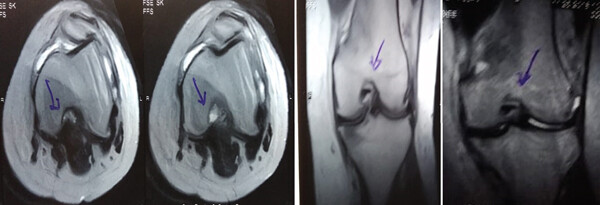

MRI:治療前后的MRI結果

治療前 MRI 顯示內側和外側半月板后角 III 級撕裂。

治療后MRI檢查顯示內側和外側半月板后角撕裂有所改善。患者癥狀改善,日常生活活動能力增強。

結論:間充質干細胞治療后,MRI檢查顯示內側和外側半月板后角撕裂有所改善 ,關節功能也有改善,未出現嚴重不良事件。可以達到干細胞治療半月板損傷短期療效的目標。

MRI檢查發現半月板損傷處修復:3D MRI 顯示 2 年時半月板撕裂難以辨別。

結論:滑膜間充質干細胞移植后,2年的隨訪中,患者的關節功能改善,MRI檢查發現半月板損傷處恢復,沒有發生導致研究終止的重大不良事件。可以達到干細胞治療半月板損傷長期療效的目標。